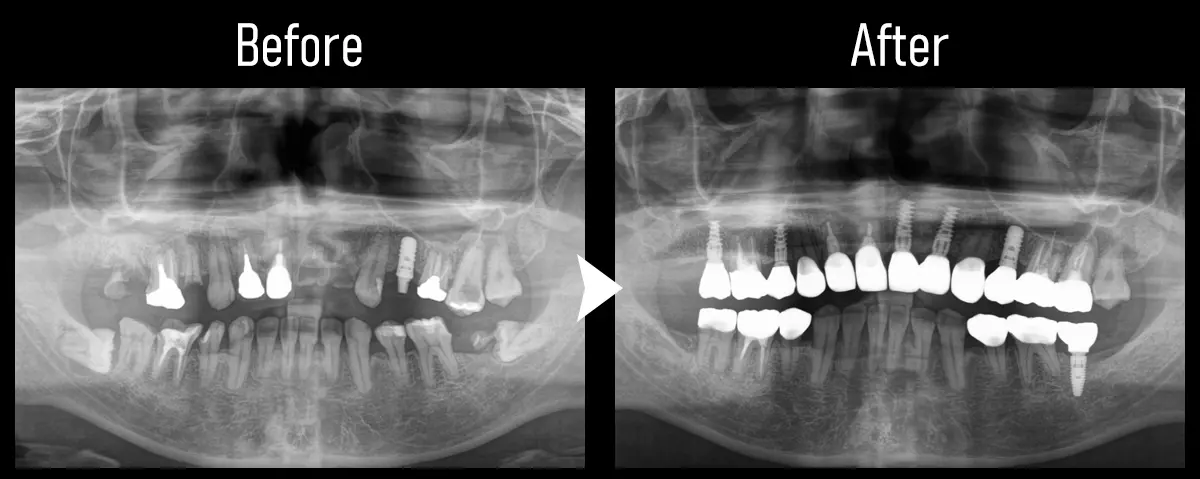

CASE:フルマウス

主訴 奥歯がない

治療内容 上下合計11本のインプラント治療を行い、全顎治療を実施

標準費用(自費) 781万円